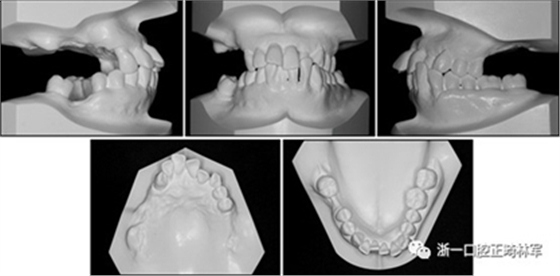

一名因多顆牙齒缺失和牙周損傷的49歲婦女被牙周科送往國民健康保險服務(wù)一山醫(yī)院的正畸科進行跨學(xué)科綜合治療。多顆后牙已在10天前被拔除。她的主訴是前牙列擁擠,她想改善美觀和功能。她的病史沒有提供有用信息,她沒有顳下頜關(guān)節(jié)紊亂的跡象??谕鈾z查顯示面部對稱,休息位時嘴唇不適,尖銳鼻唇溝和突出的嘴唇。她的下頜牙齒中線偏移到面部中線的左側(cè)(圖1)。

圖1. 治療前面部和口內(nèi)照片

口腔內(nèi)由于牙周炎,她的上頜右側(cè)第一和第二前磨牙,上頜右側(cè)第一和第二磨牙,上頜左側(cè)第一和第二磨牙以及下頜右側(cè)第一磨牙缺失。牙周探查顯示在磨牙區(qū)域和下頜骨左側(cè)側(cè)切牙區(qū)有深的牙周袋,還存在出血(表I)。上頜骨和下頜骨前牙擁擠,左側(cè)側(cè)切牙存在反合,下頜左側(cè)側(cè)切牙發(fā)過度萌出。覆蓋是5毫米,上頜切牙是唇傾的。在上頜弓中,尖牙和前磨牙是近中傾斜,右側(cè)尖牙過度萌出。而且,下頜右側(cè)第二磨牙向近中傾斜。尖牙處于I類關(guān)系,但無法評估磨牙關(guān)系(圖1和2)。

圖2. 治療前牙齒石膏模型